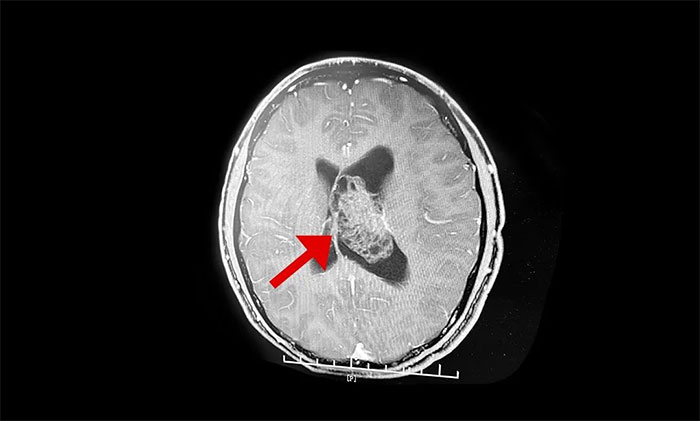

最终被诊断为中枢神经细胞瘤。中枢神经细胞瘤属于比较罕见的脑肿瘤,一般直径超过三公分即为巨大肿瘤,而李威脑室内的肿瘤直径竟达七公分,接近一个拳头大小。幸运的是,顺利手术切除。

上海蓝十字脑科医院神经外科李士其教授介绍,中枢神经细胞瘤(Central neurocytoma,CN)是少见的神经系统肿瘤,1982年由Hansson首次报道并命名,2016年WHO神经系统肿瘤组织学分类将其归类为神经元和混合型神经元胶质瘤(WHOⅡ级)。中枢神经细胞瘤仅占颅内肿瘤的0.25%~0.50%,好发于20~40岁青年人,无性别差异。病史一般较长,可达数十年之久,好发于侧脑室透明隔,当病变累及Monro孔时,阻塞脑脊液循环,引起头痛、头晕、恶性、呕吐以及不同程度视力改变等非特异性颅内高压症状。

中枢神经细胞瘤目前认为起源于室管膜下具有双向分化为神经细胞和神经胶质细胞的前体细胞。典型中枢神经细胞瘤镜下瘤细胞大小一致,圆形,核圆,居中,无核分裂像,可见神经毡、Homer-wright菊形团和神经节细胞样细胞等特异性表现。免疫组化SYN、NSE等特异性标记物表现为阳性。当瘤细胞排列呈流水状,瘤组织出现核分裂像活跃(Ki-67>2%),微血管内皮增殖、局部坏死灶时,称为非典型性中枢神经细胞瘤。

▲ 非典型性中枢神经细胞瘤